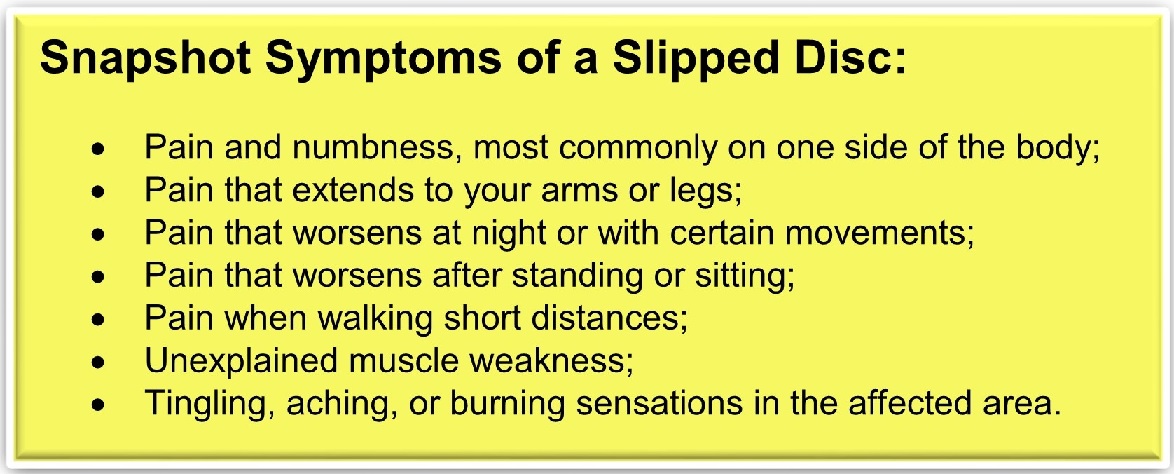

Physiatry, by its nature, involves more medical investigation and lab work to find the cause of pain. Physiatrists can achieve a lot of physical progress without the need to go under the knife. One of the most significant differences is that a physiatrist can prescribe pain medication and typically has better access to lab and advanced imaging testing.